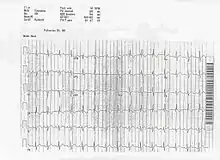

ECG of a patient with Ostium primum ASD

In the ECG above, you can see an example of the rSR' pattern in V1 with a R' greater than S with T wave inversion which is commonly seen in volume overload right ventricular hypertrophy.

On ECG a left axis deviation is generally found in ostium primum ASD, but an RSR pattern (M pattern) in V1 is characteristic. Fixed splitting of the second heart sound (S2) occurs because of equal filling of the left and right atria during all phases of the respiratory cycle.